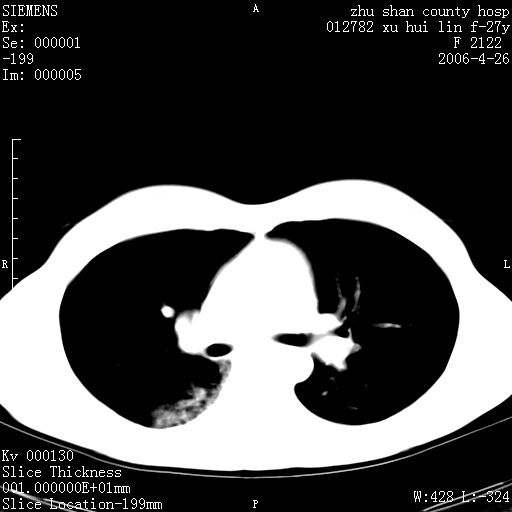

女性 病人 27岁!本院职工家属,五月前因感冒透视发现病变,ct示:左肺下叶背段感染性病变。经过半月规范抗生素治疗后复查病变无明显变化,后行四月规范抗痨治疗,复查无明显变化,后复查无效!请大家帮忙看看!

右肺下叶背段见片状高密度区,边界不清,密度不均,无钙化及空洞影,背段支气管通畅。所见层面肺门及纵隔内未见明显肿大淋巴结影。

女性 病人 27岁!本院职工家属,五月前因感冒透视发现病变,ct示:左肺下叶背段感染性病变。经过半月规范抗生素治疗后复查病变无明显变化,后行四月规范抗痨治疗,复查无明显变化,后复查无效!

诊断:首先还是考虑为慢性炎症。

结核虽然好发于下叶背段,但周围无明显卫星灶,化验结果怎样?